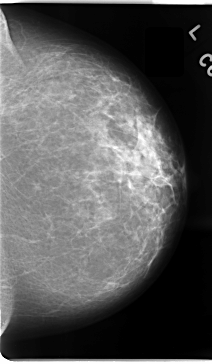

C_0094_1.RIGHT_MLO

ics_version 1.0

filename C-0094-1

DATE_OF_STUDY 5 8 1994

PATIENT_AGE 40

FILM_TYPE REGULAR

DENSITY 2

DATE_DIGITIZED 19 11 1997

DIGITIZER LUMISYS LASER

LEFT_MLO LINES 4680 PIXELS_PER_LINE 2744 BITS_PER_PIXEL 12 RESOLUTION 50 NON_OVERLAY